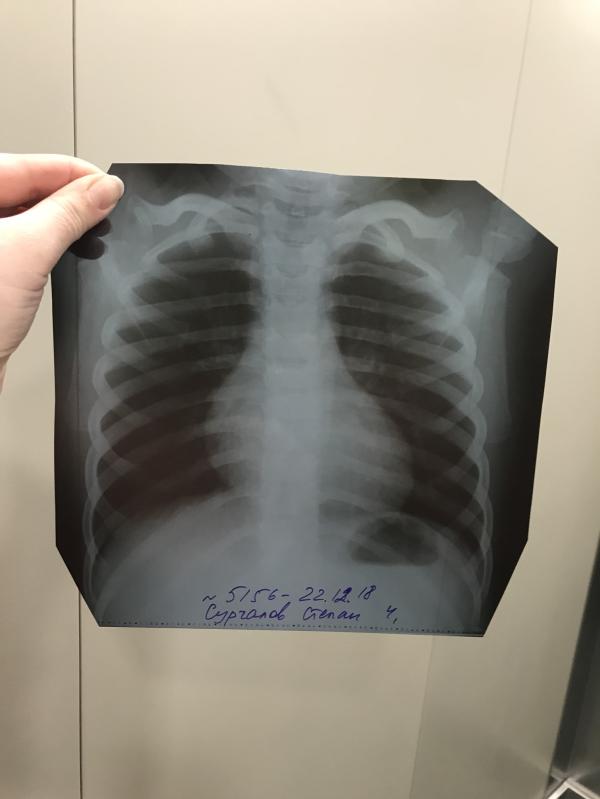

У вас поражен сегмент. Это не много. Но в аспекте ребенка - совершенно не мало. Больница, однозначно